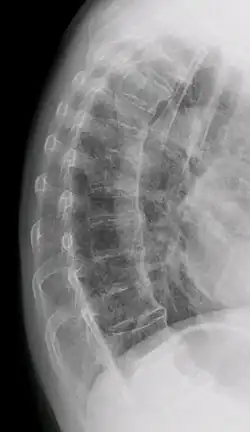

DISH in an 80 year old female, also with T11 fracture.

DISH is diagnosed by findings on x-ray studies. Radiographs of the spine will show abnormal bone formation (ossification) along the anterior spinal ligament. The disc spaces, facet and sacroiliac joints remain unaffected. Diagnosis requires confluent ossification of at least four contiguous vertebral bodies.[2] Classically, advanced disease may have "melted candle wax" appearance along the spine on radiographic studies.[13] In some cases, DISH may be manifested as ossification, or enthesis, in other parts of the skeleton.

The calcification and ossification is most common on the right side of the spine. In people with dextrocardia and situs inversus this calcification occurs on the left side.[10]